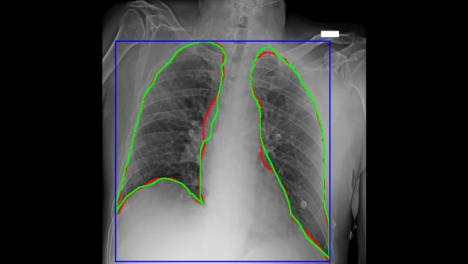

图4 AlforCOVID项目的新冠患者胸部X光片,对感染区域的AI划线(红色)与手工划线(绿色)很接近

“在对新冠患者的管理中,放射影像学对诊断和治疗方案起着至关重要的作用。得益于亚马逊云科技的技术和专业支持所带来的机器学习力量,我们已经能够快速理解诊断成像和临床分析所产生的大量数据。我们正在努力提供实用的资源,世界各地的医院和组织可以应用这种资源,增加对疾病的理解,促进自己的诊断工作,改善患者治疗。”意大利诊断中心影像诊断和立体定向放射外科主任Sergio Papa表示。